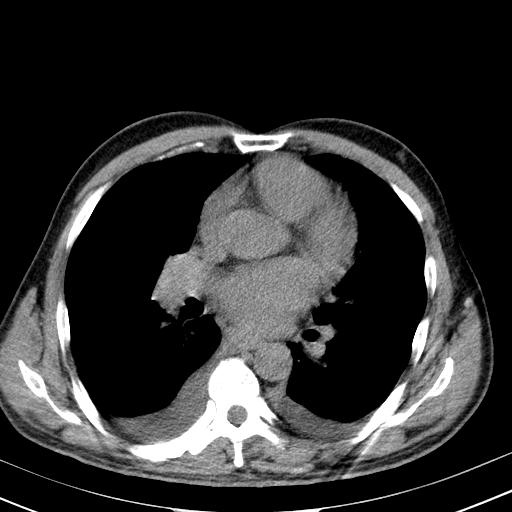

以下是引用zjzjr在2010-3-21 17:39:00的发言:[br]右下中心型肺癌并阻塞性肺炎/不张,纵膈淋巴结肿大,右侧大量胸腔积液,左侧少量胸腔积液

以下是引用zxl51642在2010-3-21 17:06:00的发言:[br]右下中心型肺癌并阻塞性肺炎/不张,纵膈淋巴结肿大,右侧大量胸腔积液,左侧少量胸腔积液,少量腹水。建议纤维支气管镜进一步检查。